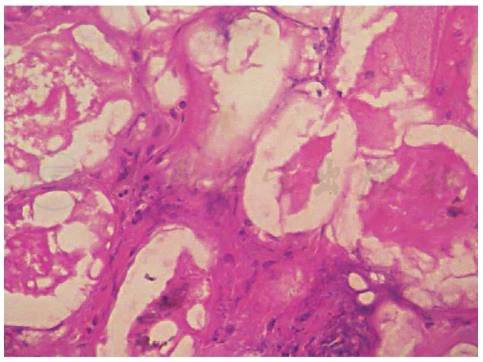

期可表现为间隔脂膜炎,间隔内血管扩张,胶原纤维增生,有淋巴细胞、中性粒细胞、多核巨细胞、少许嗜酸性粒细胞等浸润。后期逐渐出现间隔-小叶混合性脂膜炎。脂肪细胞凝固坏死,胞核消失,细胞壁变模糊,增厚,形成特征性“鬼影细胞”。脂肪被钙盐皂化生成嗜碱性物质,呈颗粒状或均质状沉积。病程晚期纤维化,脂肪组织萎缩(图1~图3)。

图2胰腺性脂膜炎病理(二)

引自:朱德生皮肤病学.第5版.ISBN:978-7-117-29665-6.主编: